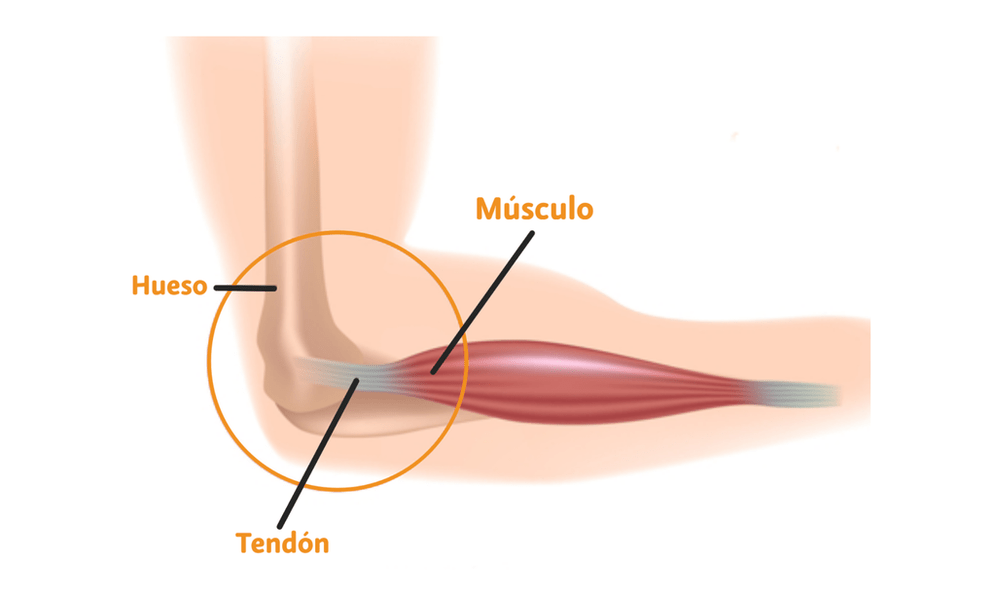

Para poder entender que es un desgarre y cuales son sus características, primero debemos entender que es un musculo y tendón.

El músculo es una estructura compuesta por fibrillas o filamentos agrupadas que tiran en dirección concéntrica (hacia el centro del músculo), genera una tracción capaz de mover el cuerpo y sus diferentes segmentos.

Por otro lado el tendón es una estructura no tan flexible en comparación con el músculo, es la unión entre el hueso y el músculo.

Transmite el movimiento. De igual manera formado por filamentos compuestos de colágeno y elastina, que le da su capacidad de resistir la tensión resultante por la contracción muscular.